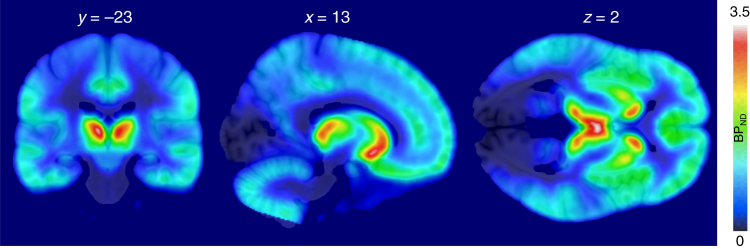

Fig. 2.

Mean distribution of MOR in the brain as measured with [11C]carfentanil (n = 33) showing widespread MOR expression with highest densities in striatum, thalamus, and cingulate cortex